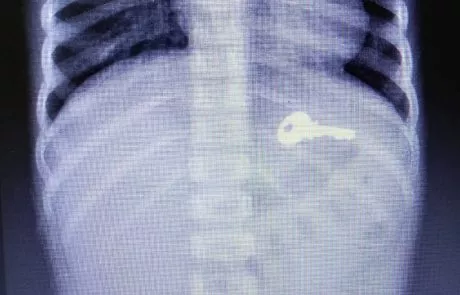

פעוט בן כשנתיים וחצי בלע מפתח בעת שהוריו עסקו בהכנות לחג.

המפתח הוצא מקיבתו בגסטרוקופיה שבוצעה במרכז הרפואי בני ציון